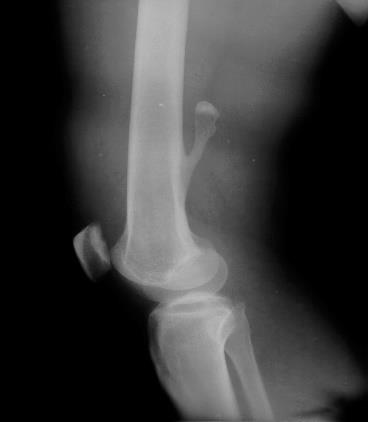

2)尤因肉瘤

①年龄:儿童

②好发部位:股骨、胫骨、尺骨

③进行性疼痛,夜间重,伴发烧

④局部肿块,有压痛

⑤化验:白细胞多,血沉快.X线葱皮反应

⑥对放疗极为敏感、预后差;截肢或保肢手术效果也不理想;化疗也很有效,能延缓转移。现采用放疗加化疗和手术的综合治疗